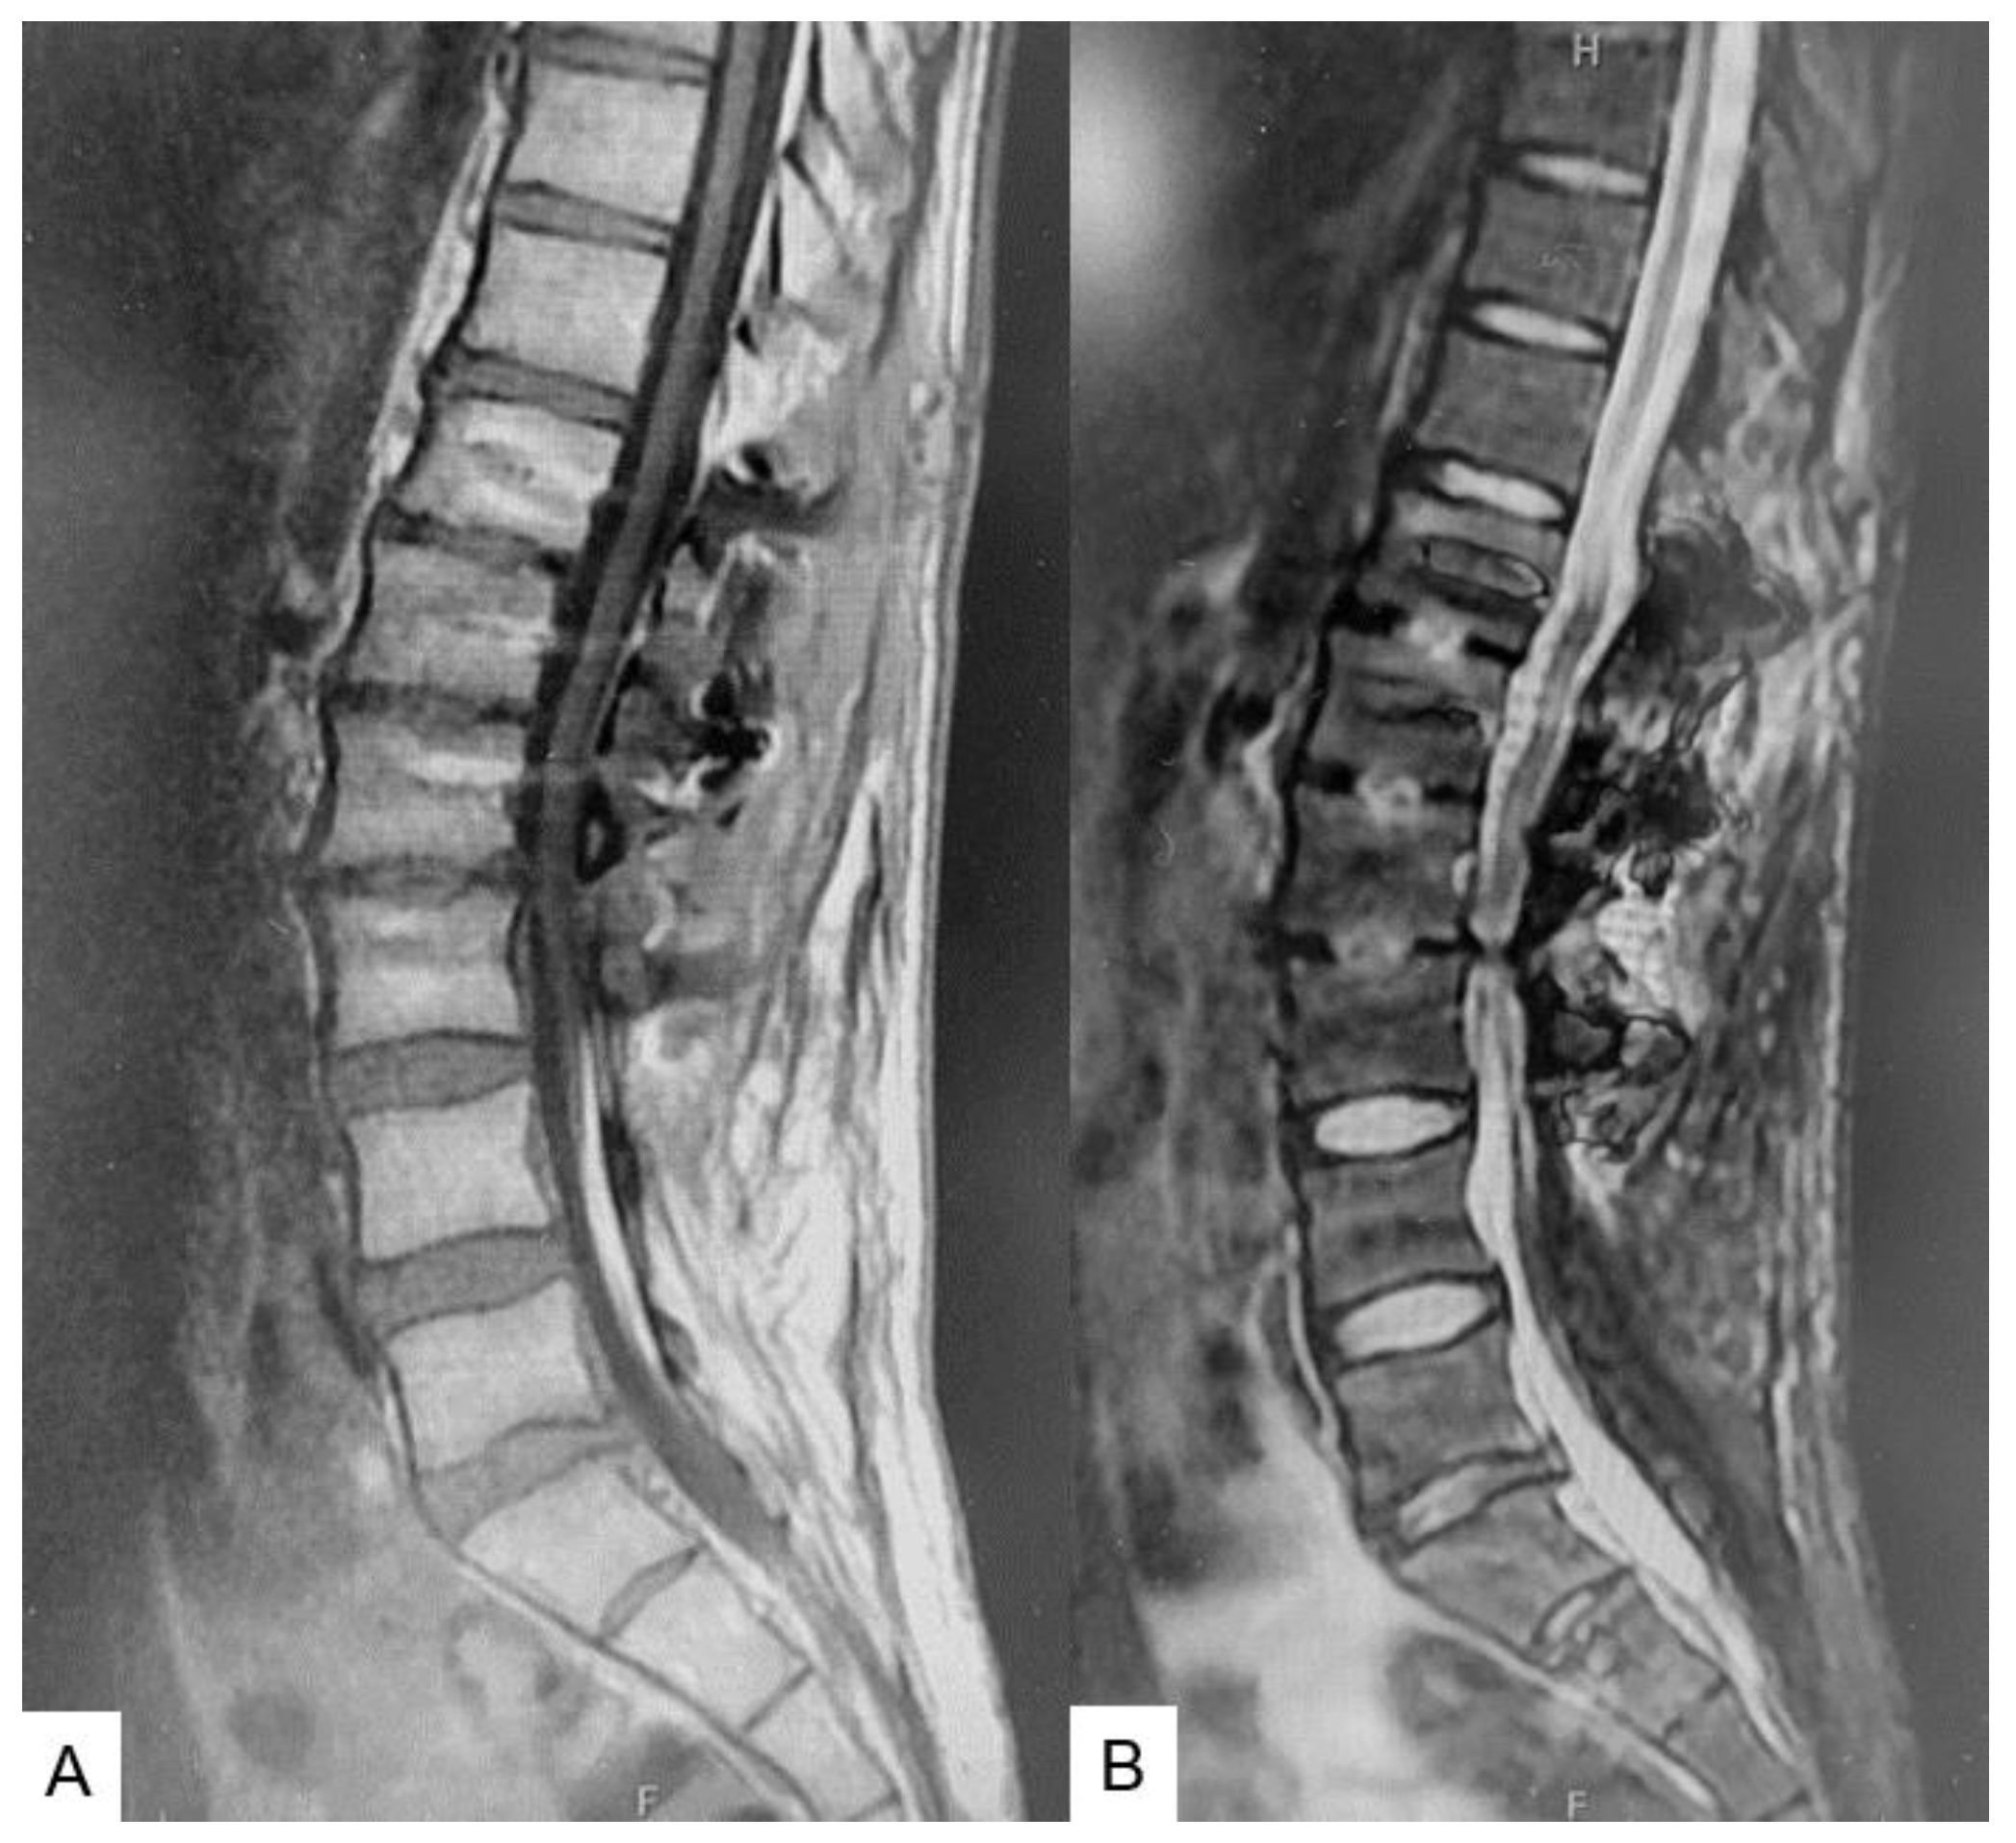

2.3. Preoperative imaging

3. Case 2 33 years old male, tethered cord syndrome, conventional technique